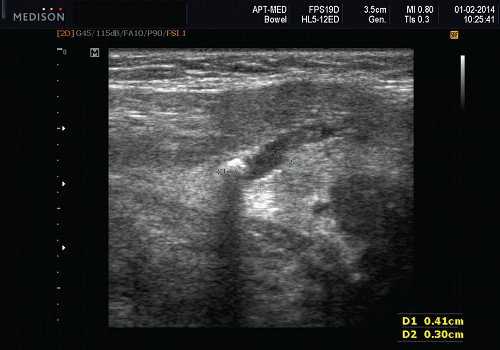

- Лучший диагностический признак на УЗИ слюнной железы - Увеличенное солидное образование околоушной или поднижнечелюстной железы

- Размер 1-5 см.

- Серошкальное УЗИ. Одиночное солидное образование в паренхиме околоушной или подчелюстной железы. Может иметь хорошо выраженные, дольчатые или плохо очерченные / инфильтративные границы. Гипоэхогенная структура по отношению к паренхиме слюнной железы. Общее улучшение ультразвукового изображения задних структур. Иногда центральный кистозный компонент представляет некроз. Могут наблюдаться связанные аномальные интрапаротидные, перипаротидные, шейные лимфатические узлы

Визуализация. Общие особенности. Само по себе ультразвуковое сканирование метастазов в околоушные лимфоузлы неспецифична. Одиночные или множественные околоушные образования. Хорошо выраженный или плохо выраженный лимфоузел (экстранодальное распространение), однородный или неоднородный с внутренним некрозом. На УЗИ с ЦДК внутриузловая васкуляризация или усиление кровотока. Патология связана с известным первичным раком, часто в прилегающей коже или региональной области головы и шеи. Околоушные и перипаротидные узлы: узловая станция 1-го порядка при плоскоклеточной карциноме кожи (ПКК) и меланоме латеральной части волосистой части головы, ушной раковины / наружного слухового прохода и передней части лица

Размер. Обычно 1-3 см

Серошкальное УЗИ. Одиночные или множественные гипоэхогенные образования в известном распределении внутрипаротидных лимфоузлов. Хорошо выраженный или слабо окаймленный (экстранодальное распространение). Экстранодальное распространение. Обратите внимание на местную инвазию интрапаротидной наружной сонной артерии (ВСА), ретромандибулярной вены или экстрапаротидных мягких тканей. Аномальная внутренняя архитектура ± эхогенные ворота. Однородный или неоднородный вид с внутренними кистозными участками в некротических узлах ± метастазы в шейные лимфатические узлы